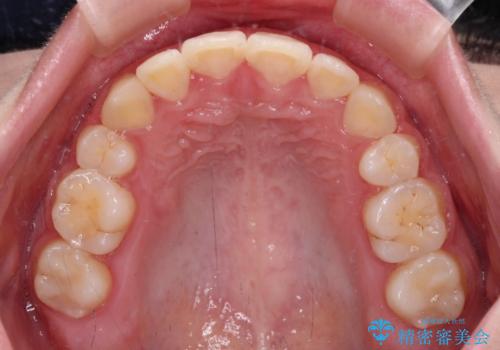

- 八重歯やデコボコをインビザラインで治療したいとのことで来院された患者様です。

インビザライン単体で治療を行うには叢生が強いと判断されたため、事前にワイヤー装置で抜歯矯正を行い、ある程度改善してからインビザラインにて仕上げていくこととしました。